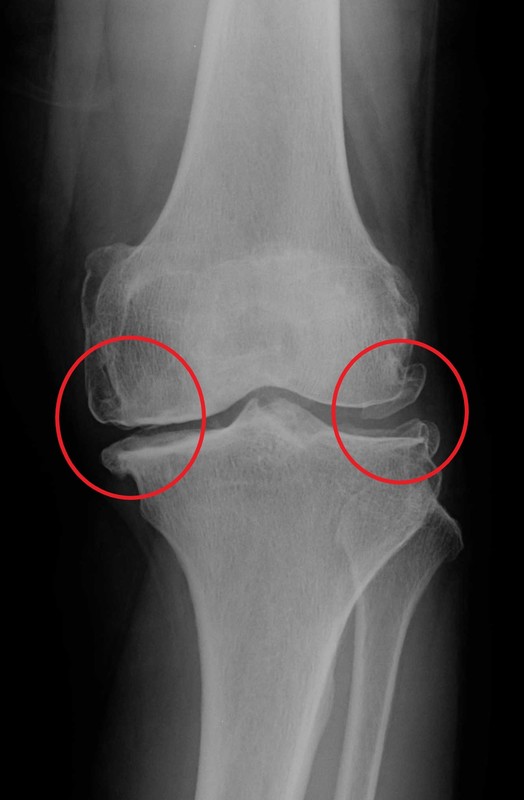

前十字靭帯が断裂すると膝の踏ん張る機能が破綻され、膝が不安定になります。年齢を重ねるごとに、筋力は低下していきます。その状態で日常生活やスポーツをしていると膝への負担は大きくなります。膝への負担が大きくなることで、不安定な膝を安定させようと膝に棘のようなものができたり、O脚変形(図)が早くなると言われています。このようになってしまうと、運動したときに膝が痛くなってしまいます。進行していくと、歩行や階段昇降で膝が痛くなることもあります。また、膝に水が溜まって腫れる場合や膝の可動域制限(膝の曲げ伸ばしがしにくい)などの症状も出ることがあります。